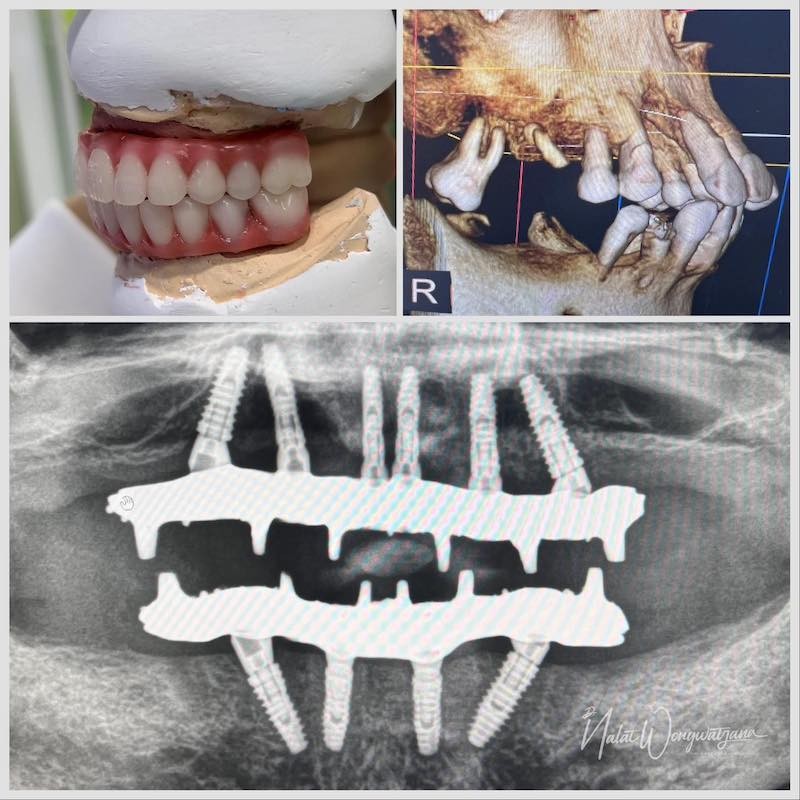

DENTAL IMPLANT-รากฟันเทียม

ด้วยประสบการณ์มากกว่า 10 ปีในงานฟื้นฟูช่องปากทั้งปาก (Full-Mouth Rehabilitation) และเทคนิคการฝังรากเทียมแบบดิจิทัล (Digital Guided Surgery)